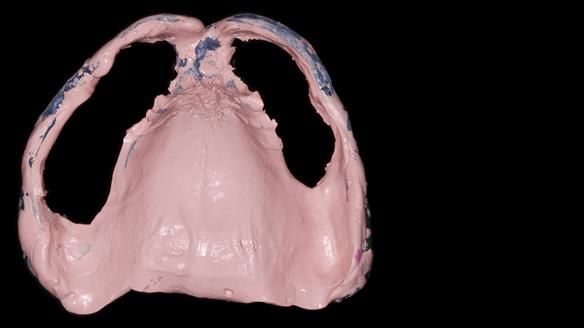

We provided her with an immediate upper denture (Mk 1), followed by a definitive metal-based upper denture (Mk 2). A lower removable partial denture was discussed, to be made only if needed once the upper treatment was complete. However, at review, this wasn’t necessary — Adnana had excellent neuromuscular control and function, even with a shortened dental arch (SDA).

Rowan, Sam Hesketh and Chris Hesketh provided the stunning technical work. I am very lucky to have them.